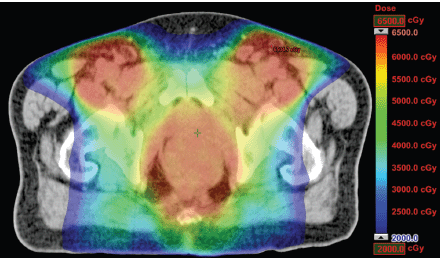

The IMRT achieved better dosimetric results in all organs tested in both the male and female patients. Compared with conformal radiotherapy, IMRT dose was reduced by 59% in the bladder, 14% in the intestine, 41% in the genitals, 26% in the iliac wings, 75% in the femoral heads and 14% in healthy tissue. The integral doses for all organs were lower with RapidArc® than with the sliding window IMRT or the conformal radiotherapy (Table 3, Figures 1–5).

Figure 1. Dosimetric results obtained with RapidArc.